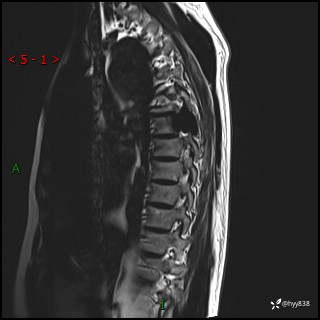

胸椎MRI平扫(sag T1WI+T2WI)